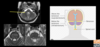

MRI can be used to diagnose patients with multipole sclerosis. But MRI must be used alongside the McDonald criteria. One finding is called dissemination in space? 1 - lesions are present in the open space of the ventricles 2 - lesions are present in the intracranial space 3 - lesions are visible throughout the brain 4 - all of the above

3 - lesions are visible throughout the brain - >1 T2 (bright) lesions in at least 2 of the four areas of the CND 1 - juxtacorticol 2 - periventricular 3 - infratentorial 4 - spinal cord

When we talk about lesions in multiple sclerosis, they can be - juxtacortical/intracortical - periventricular - infratentorial - spinal cord Which of the above areas of the CNS matches the following: - lesion in cerebral white matter abutting (overlapping) the cortex

- juxtacortical - juxta = next to/overlapping - cortical - cortex - these occur in the white matter (neuronal myelin) and overlap the grey matter

34

When we talk about lesions in multiple sclerosis, they can be - juxtacortical/intracortical - periventricular - infratentorial - spinal cord Which of the above areas of the CNS matches the following: - lesion in cortex

- intracortical - intra = inside - cortical - cortex - these occur within the grey matter, neuronal cell bodies

35

When we talk about lesions in multiple sclerosis, they can be - juxtacortical/intracortical - periventricular - infratentorial - spinal cord Which of the above areas of the CNS matches the following: - lesion next to and with direct contact with the lateral ventricles

- periventricular - image shows bright demyelination plaques around the lateral ventricles

36

When we talk about lesions in multiple sclerosis, they can be - juxtacortical/intracortical - periventricular - infratentorial - spinal cord Which of the above areas of the CNS matches the following: - below the tentorium (cerebellum, pons, brainstem)

- infratentorial - can resemble small vessel disease